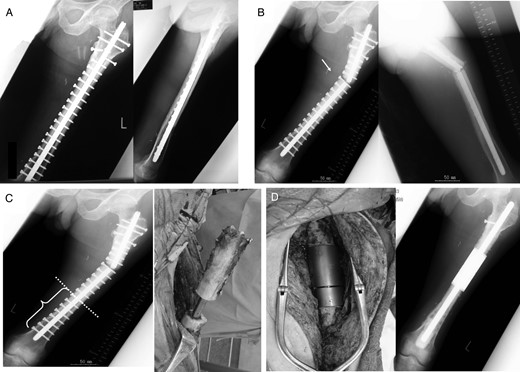

Case 2: A 71-year-old female was treated at the age of 68 for metastatic synovial sarcoma of the femur (Fig. 3A). Wide en bloc resection of the tumor and reconstruction with the use of IORBG were performed (Fig. 3B). At 32 months later, distal thigh pain due to fracture of the graft and breakage of plate occurred (Fig. 3C). Failed graft bone resection, implant removal and reconstruction with custom-made intercalary endoprosthesis were performed (Fig. 3D). The best MSTS score was 25 of 30. Aseptic loosening occurred at 29 months after the first endoprosthetic replacement which required a revision procedure (Fig. 3E and F). This was associated with osteolysis around the distal femoral end of the prosthesis.

A 68-year-old female with metastatic synovial sarcoma in right femoral diaphyseal bone. Plain radiograph and MRI (A) showing metastatic bone tumor. Radiograph (B) showing wide resection included femoral diaphyseal bone and reconstruction with IORBG and plate. At 32 months after surgery, radiograph (C) showing graft bone fracture (arrow) and reconstruction with intercalary endoprosthesis (D). Aseptic loosening occurred 29 months after surgery (E), and revision surgery was performed (F).